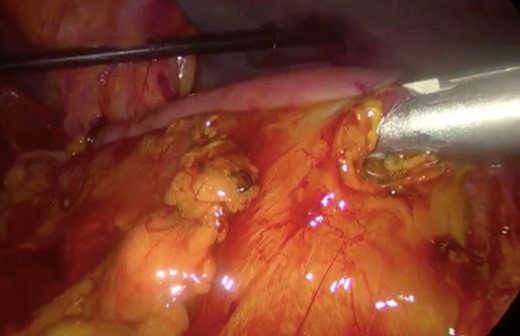

Initially, conservative management was adopted with some improvement of patient’s nutrition condition. However, as symptoms persisted, surgical treatment was recommended. Our surgical approach was a laparoscopic duodenojejunostomy with a latero-lateral stapled anastomosis between jejunum (30 cm from Treitz’s angle) and the second portion of the duodenum (Figs 5–9). The patient recovered with no pain but with a delay in diet acceptance. An upper GI contrast study was performed on the fifth post-operative day revealing a distended stomach with gastric emptying delay, but with unobstructed anastomosis, therefore without stenosis or leaks (Fig. 10). She was discharged home after 8 days with liquid diet and digestive transit restored. After 3 months of follow-up, the patient gained some weight and remained asymptomatic.

Surgery—laparoscopic stapled anastomosis between jejunum and second portion of duodenum.